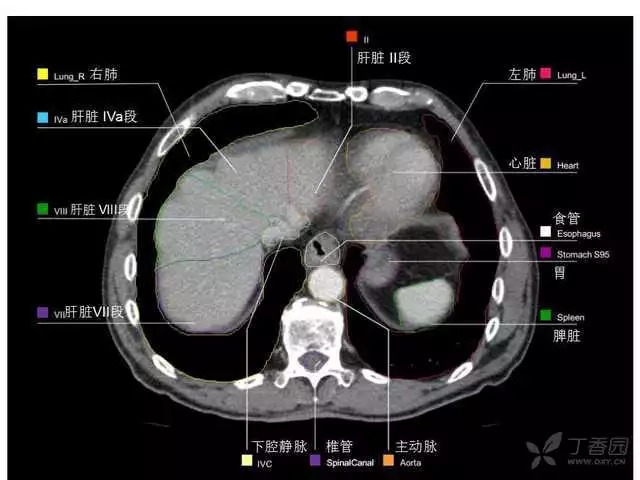

腹部肝脏高清CT断层的图谱

全腹部高清CT图谱,淋巴结彩色图谱,血管解剖图谱大汇总!

超声肝脏分叶及分段

肝脏分段和基本解剖学标志